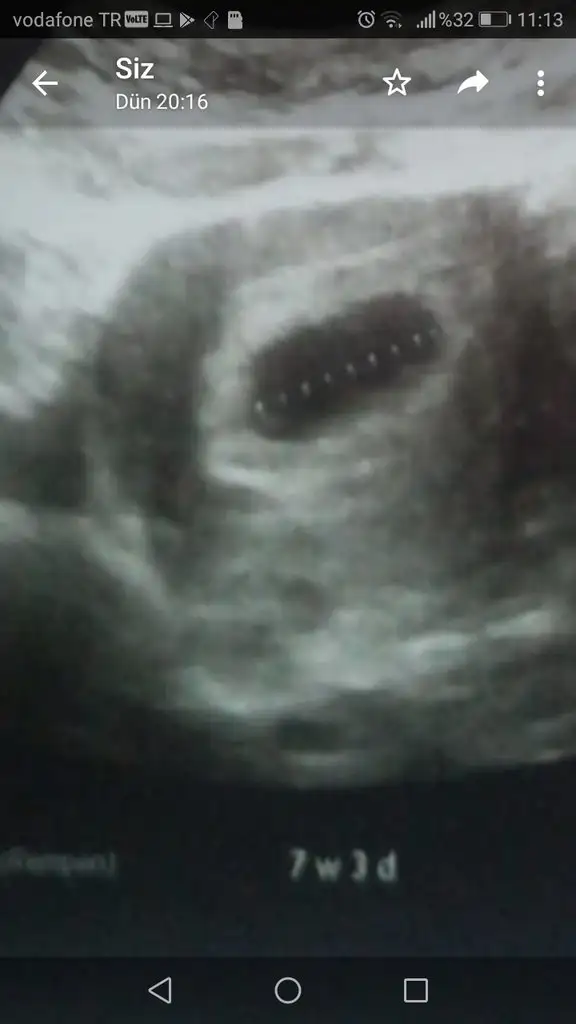

Evet 6 haftalıkken kalp atışını bende de doktor duymuştu ben duymamıştım daha çok yeni demişti ama bir hafta sonra ben de duymuştum.Değerlere gelince bazı değerlerin düşük olması tek başına ifade etmiyormuş diğer değerle değerlendiriliyormuş.Ama ultrason görüntüdeki hafta hesaplamayı anlamadım.Herkese günaydın . Dün 6+1 kalp atışımızı dr gördü sizin duyabilmeniz için daha erken dedi . çogunuzun bahsettiği şişilk bendede var zaten kiloluyum birde karın çıktı hamile kıyafeti almaya gidecegim bugün. Pantalonlarım çok rahatsızlık veriyor artık dügme acık dolanıyorum işyerindetroidden dolayı düşük riskimin oldugunu dikkat etmemi söyledi dr . Akşam ultrason çıktılarında fark ettim birinde kese ölçümü yapılmış 7+3 yazıyor digerinde bebek ölçümü var 6+1 sorun olsa dr um söylerdi ama yinede aklıma takıldı aynı sey olan varmı ?